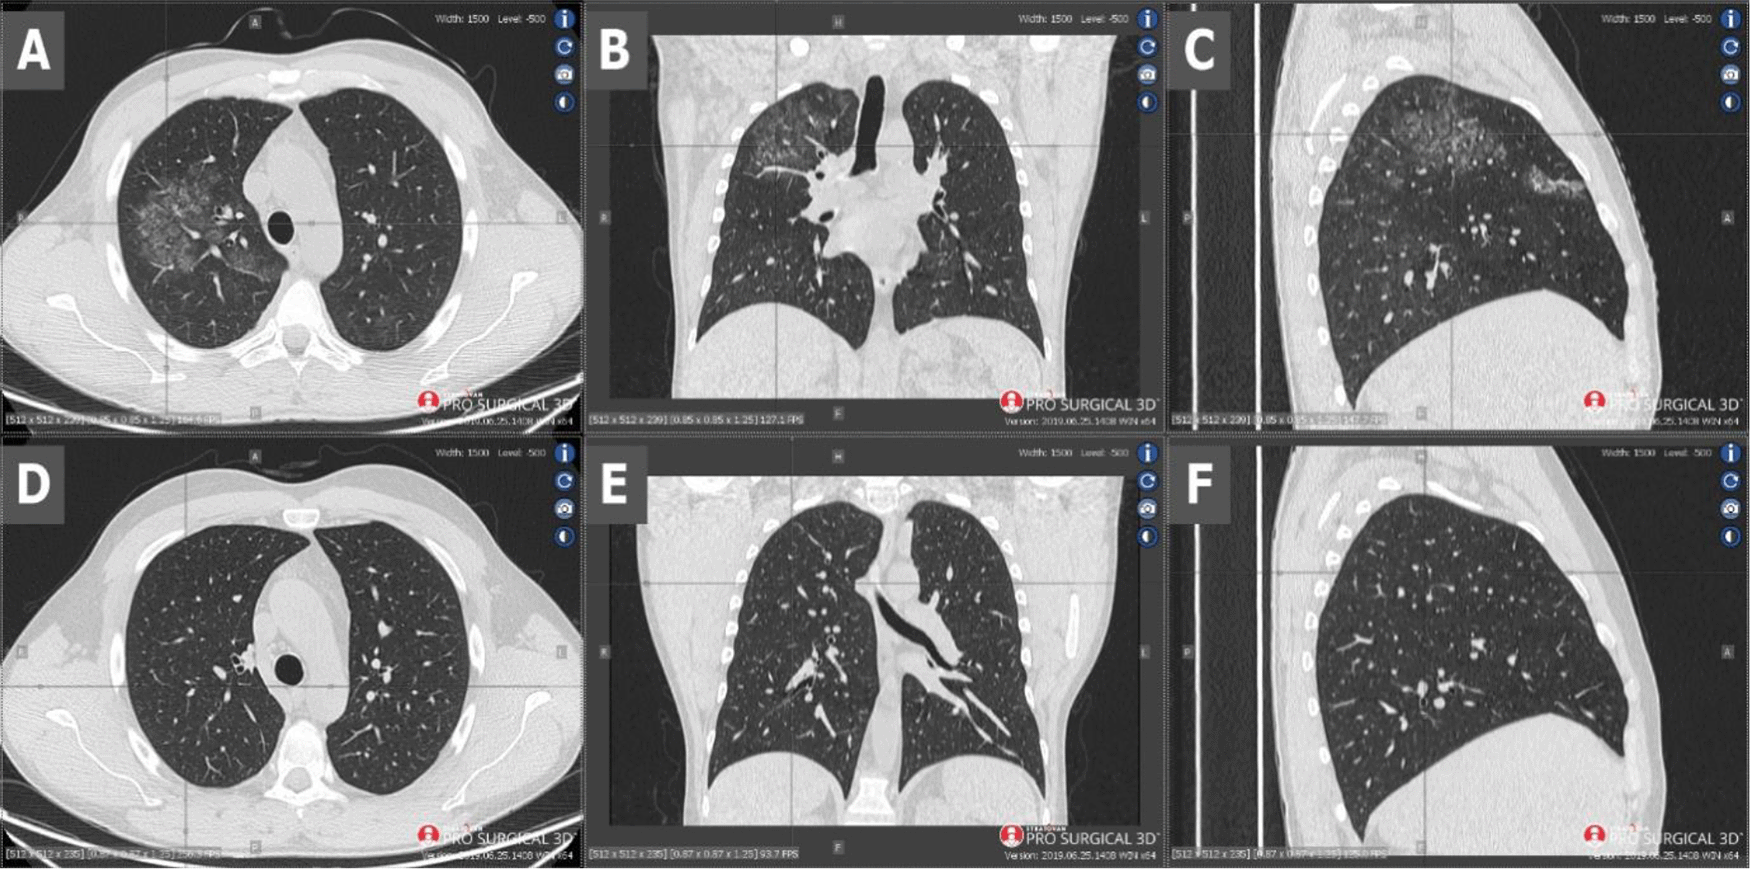

Owing to the anamnesis of transient arthralgia and rapid deterioration of the kidney function, antibody panel was carried out in which anti-glomerular basement membrane antibodies (anti-GBM), antinuclear antibodies (ANA), as well as cytoplasmic anti-neutrophil cytoplasmic antibodies (c-ANCA) were negative, whereas perinuclear anti-neutrophil cytoplasmic antibodies (p-ANCA) were found with a high titer (>200; N: <1:20), suggesting p-ANCA vasculitis complicating COVID-19. Laboratory tests revealed AKI requiring haemodialysis. Anaemia was particularly noticeable. Additionally, leukocytosis, hypoproteinemia, dysproteinemia, elevated D-dimers, C-reactive protein (CRP), interleukin 6 (IL-6), creatinine and urea levels, proteinuria and haematuria were present (Table 1). The parameters of the blood coagulation system were within normal range. Chest computed tomography (CT) demonstrated changes suggesting both viral pneumonia and alveolar haemorrhage (Figure 1, scans A-C). Kidney biopsy performed on the first day of hospitalisation in the Nephrology Clinic and examined with a light microscope revealed crescents in segmental tuft necrosis in two, cellular crescent in one and fibrocellular crescents in three out of nine glomeruli. Glomerular lesions were accompanied by mild interstitial inflammation and acute tubular necrosis. There was no interstitial fibrosis nor tubular atrophy. Immunofluorescence did not reveal any deposits of immunoglobulins nor complement components (Figure 2). The biopsy result, combined with clinical manifestation, prompted the diagnosis of rapidly progressing glomerulonephritis (RPGN) in the course of p-ANCA vasculitis.

Scans A-C - CT performed on admission - scans show diffuse ground-glass opacities and septal interlobular thickening in the right lung, as well as paving-stone findings which could represent alveolar haemorrhage. Scans D-F - CT performed 2 months later - visible radiological regression.

Currently, immunotherapy is continued. To date, the patient has received a total of 2.4 g (four cycles of 600 mg each, 3 weeks apart) of cyclophosphamide. The therapy is well-tolerated and a pulmonary clinical and radiological remission has been achieved (Figure 1, scans D-F). Additionally, renal parameters have improved with creatinine level at 1.1 mg/dl and stable proteinuria of 1.8 g/24 h.

Despite the fact that COVID-19 could have been the reason for pneumorrhagia and such severe state of the patient, systemic vasculitis seemed to be the more likely cause. Thus, the limitation of vasculitis effects and induction of immunosuppression was essential. To this end, plasmapheresis and high doses of IVIG were ordered. It is worth noting that IVIG and plasmapheresis could limit a SARS-CoV-2 infection and increase the tolerance to immunosuppressive treatment4 which was twice as beneficial for our patient. The patient also received remdesivir to inhibit the virus multiplication and invasion. It should be noted that starting immunosuppression in the acute phase of the disease was very risky. Surprisingly, not only did cyclophosphamide not harm the patient, but also the whole applied treatment improved the patient’s state remarkably. CT performed 32 days after the initial CT (after three cycles of cyclophosphamide) showed total regression of ground-glass opacities and septal interlobular thickening and paving-stone findings (Figure 1, scans D-F), even though radiological changes in the lungs in COVID-19 can persist for a long time after recovering from the disease.5